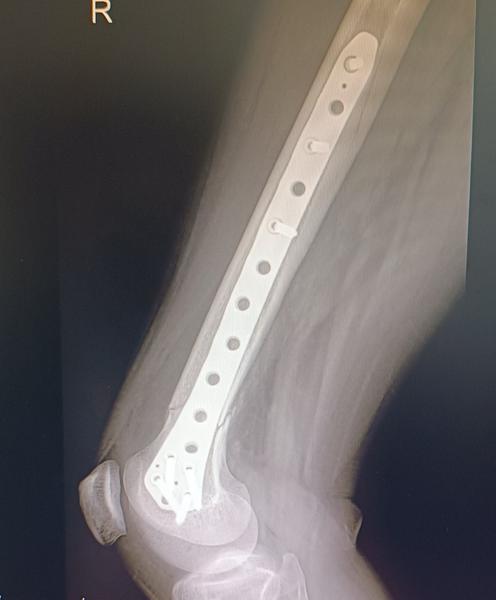

Dobrý deň prosím ak tu taky su napíšte mi ako ste to zvladali cele ...ja mam v nohe stehenna kosť platničku plus skrutky o mesiac mam planovanu operáciu na vybratie materiálu mam 35 rokov môžem si to ešte premyslieť a zrušiť mne platnička nerobi nejake výrazne problemy ,nohu mam akurat taku oťaženu krivam stale ale ja som vďačná že vôbec chodím..v zime ma bolievalo koleno pri dlhej chodzi neviem či z platničky alebo tym že noha bola zlomena ..nepovedia mi to ani lekari ani ty sa nezhodnu v tom či platničku nechať alebo vybrať a ja som s toho na prašky čo je lepšia možnosť 🥺😢 bojim sa operacie hrozne moc mam doma dve male deti desim sa toho zas prechádzať tým čím pred vyše rokom pre mňa to celé bola trauma , ale zas sa bojim aj toho aby mi to neskôr nerobilo problémy momentálne som ešte na rodičovskom a keď nastupim do práce by som možno mohla byť už fit keby mi to teraz vyberu neviem čo robiť som zufala😔